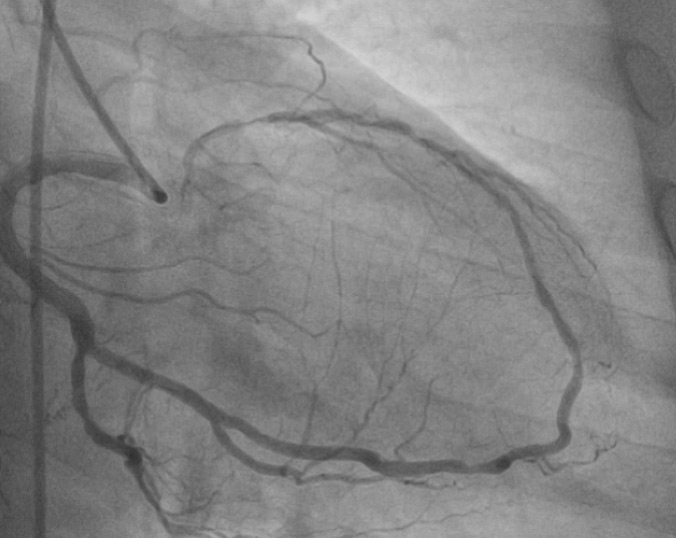

Tangled web